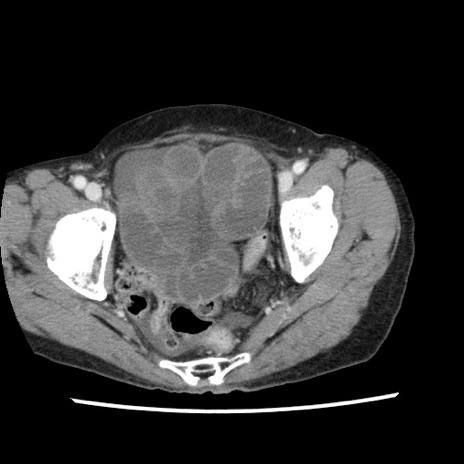

【症例】80歳代女性

【主訴】腹痛

【現病歴】8時間前から腹痛あり来院。

【既往歴】糖尿病、脂質異常症、子宮体癌にて子宮全摘術

【身体所見】意識清明・会話良好だが腹痛で苦悶様、全腹部にわたって反跳痛と圧痛あり

【データ】WBC 13600、CRP 0.14、LDH 224、CK 90